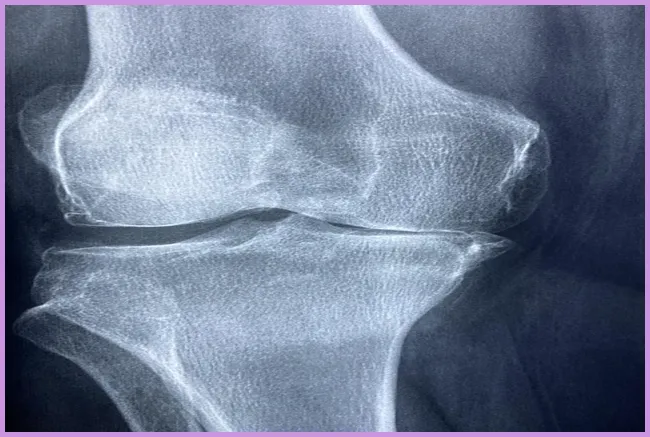

퇴행성 관절염의 원인과 증상

퇴행성 관절염은 주로 노화와 관련이 깊습니다. 나이가 들면서 관절의 유연성이 떨어지고, 연골이 줄어들어 통증을 느끼게 됩니다. 또한 비만, 과도한 운동, 유전적 요인 등이 퇴행성 관절염을 악화시킬 수 있습니다. 주요 증상으로는 관절의 경직, 통증, 불균형 등이 있습니다. 이런 증상을 경험할 때면 일상적인 활동도 어렵게 느껴지곤 하지요.